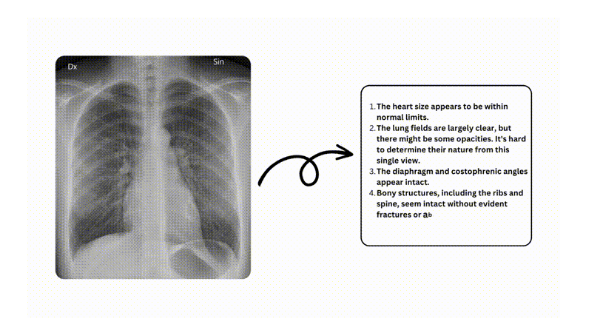

엑스레이 인터프리터는 인공지능의 힘을 활용하여 엑스레이 이미지에 대한 예비 판독을 제공하는 의료 진단 AI 서비스입니다. 공식 웹사이트 xrayinterpreter.com을 통해 액세스 할 수 있는 이 도구는 편의성, 정확성, 개인정보 보호의 독특한 조합을 제공하며, 의료 전문가와 엑스레이 결과에 대한 분석과 인사이트를 얻고자 할 때 유용하게 사용할 수 있습니다.

단순한 알고리즘 이상의 AI 판독기술엑스레이 인터프리터는 AI 기술을 사용하여 흉부, 치과, 복부 및 골격 구조를 포함한 몸 구석구석 다양한 유형의 엑스레이 이미지를 분석합니다. 사용자가 업로드한 이미지에 대해서 AI가 빠르게 의료기관 진단이전이나 이후에 예비 판독해 볼 수 있습니다.

AI가 생성한 해석받기

이미지를 업로드한 후 '제출' 버튼을 클릭하세요. AI 시스템이 몇 분 안에 판독 결과를 생성하고, 엑스레이 이미지 판독이 포함된 자세한 보고서를 받게 됩니다.

정확도 및 신뢰성